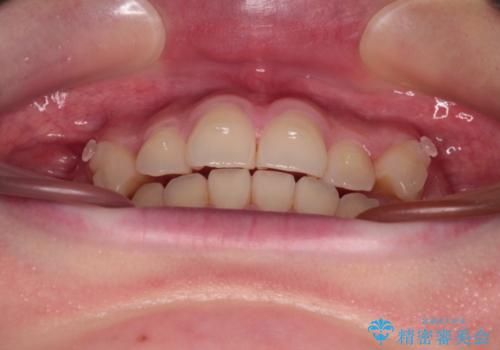

- 左右の八重歯を気にして来院された患者様です。

歯列としてはインビザラインでもワイヤー矯正でも対応できるものでしたが、インビザラインによる治療を希望されていました。

上顎の八重歯改善にインビザラインでは時間のかかってしまう可能性があり、更には口元が治療前よりも突出してしまう可能性があったため、補助装置により八重歯を事前に引き込んでおくことで、インビザラインによる治療をスムーズに行えるように計画しました。

補助装置を使用したことで、口元が突出することもなく、スムーズに仕上げることができました。